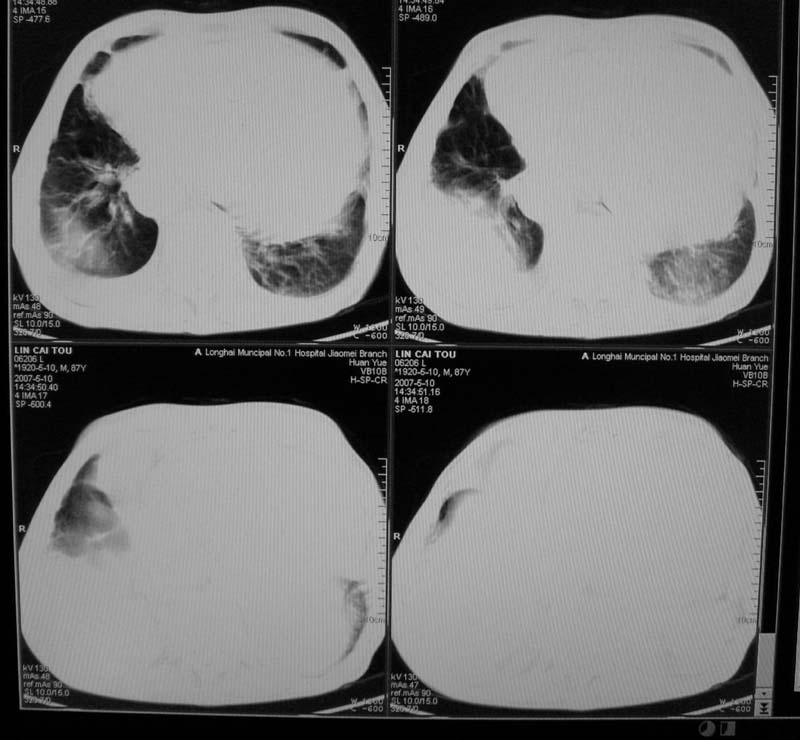

以下是引用小初学者在2007-5-12 16:26:00的发言:[br]1、心衰肺水肿两侧胸腔积液2、心包积液3、心瓣膜钙化